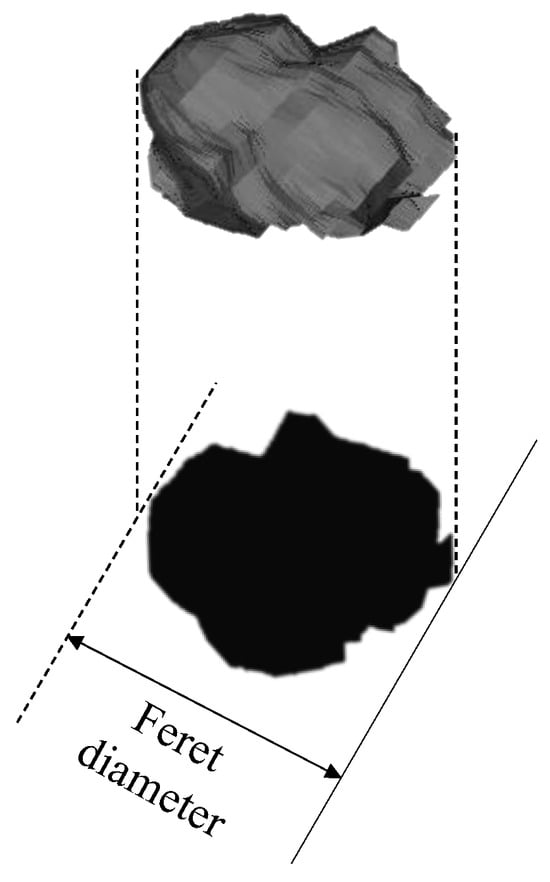

2.5. Prediction of CTR